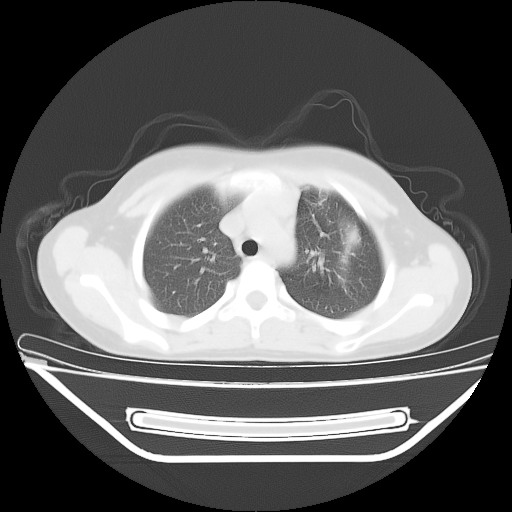

女,12岁,前期发热,咳嗽,无痰,经头孢抗炎无效。ct右肺上叶实变影.5天后公布病理结果。以下是2010-2-13ct片

定位肺外,年龄小,还是先考虑畸胎瘤,左上肺膨胀不全并炎症。

鉴别:内胚窦瘤恶性程度高,有胸水;淋巴瘤、胸腺瘤、sftp等年龄大;异物上叶少见,无肺气肿及纵膈偏移不支持;炎症定位不考虑肺内所以排除。

考虑畸胎瘤破溃并左肺上叶炎症。

左前上纵膈可见大块影,与大血管关系密切,邻近肺少许炎症,考虑左前上纵膈占位,胸腺瘤或畸胎瘤,并左上肺膨胀不全。

经过胸部穿刺活检为支原体感染。以下示抗支原体感染30天后所见,病灶明显缩小,临床症状消失: